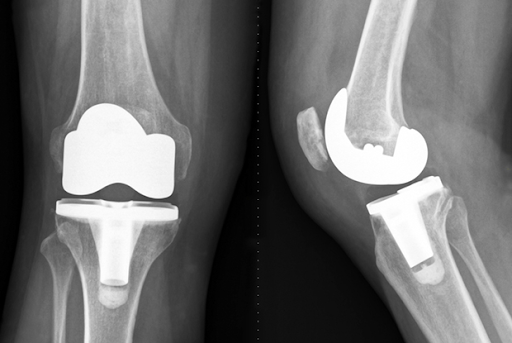

Implant Placement

The surgeon attaches metal components to the prepared bone surfaces. A plastic spacer sits between these components to allow smooth movement.